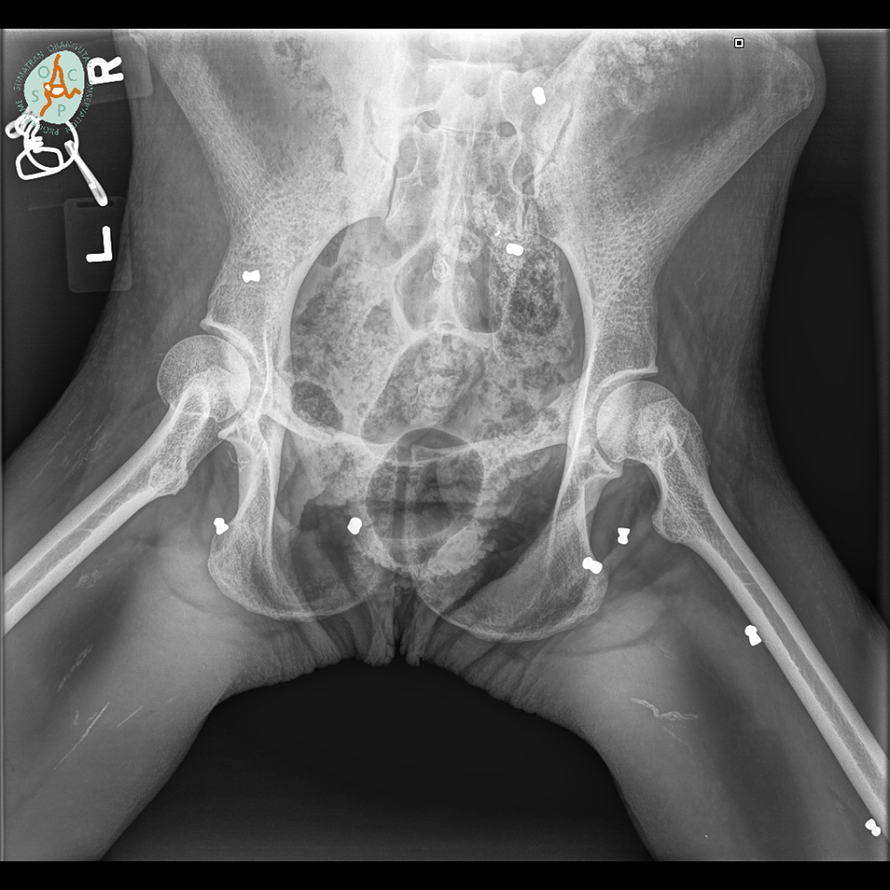

Stravična sudbina orangutana: Upucali ga iz zračnice 74 puta

Sudbina orangutana Hope je najstrašnija od svih ozlijeđenih životinja na koje smo ikad naišli. Nezamislivo je da ovakvo nešto može napraviti čovjek, kažu u Organizaciji za očuvanje orangutana na Sumatri